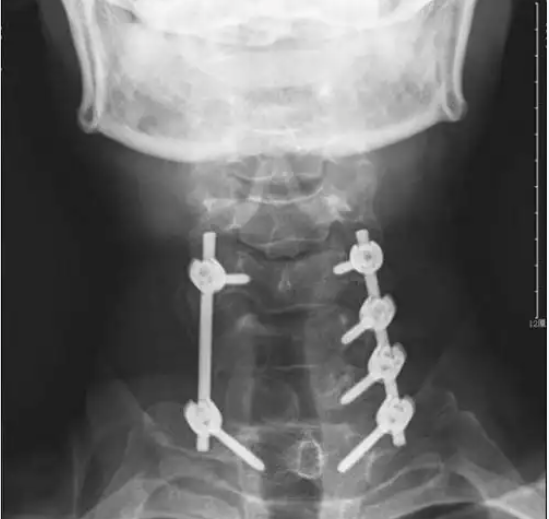

Clinical Scenario – The Patient with L4-L5 Spondylolisthesis

A 62-year-old with degenerative spondylolisthesis at L4-L5 and symptomatic stenosis undergoes a lumbar cage fusion posterior (PLIF). Bilateral laminectomy and facetectomy decompress the thecal sac and nerve roots. Two PEEK cages packed with local autograft are inserted into the disc space from left and right. Pedicle screws and rods are placed at L4-L5. Postoperative X-rays show restored disc height and normal alignment. The patient wears a brace for 6 weeks and returns to walking at 2 weeks. At one year, the fusion is solid, and leg pain is resolved.